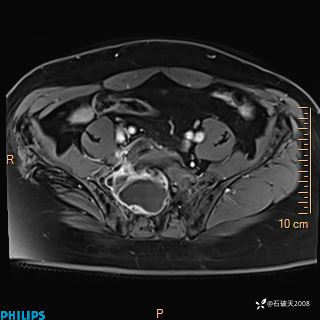

2023年3月份MRI影像

增强轴位